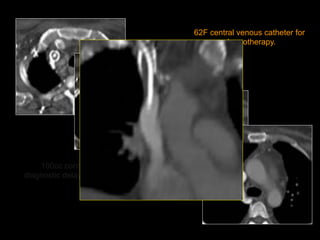

62F central venous catheter for

chemotherapy.

100cc contrast,

diagnostic delay = 60sec